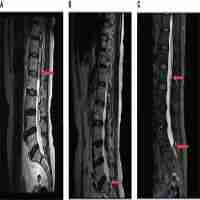

| Abstract | Background: As angiogenesis is an essential step in tumor growth and metastasis, the tyrosine kinase inhibitor (TKI) apatinib has become a revolutionary anticancer therapy across various malignancies. However, its efficiency and safety in Merkel cell carcinoma (MCC) are uncertain. Case presentation: The current study described the case of a 91-year-old man who presented with a 3.2×3.0×2.2 cm rapidly growing, solitary tumor of the right lower eyelid. It was diagnosed as MCC pathologically. Twenty-seven days after the surgery, the patient returned to the hospital with recurrent MCC. Apatinib was then administered to this patient. The patient had a complete response (CR) to apatinib after 4.4 months of targeted therapy. Twenty-seven months of progression-free survival (PFS) was achieved with controllable treatment-related adverse events (AEs). Conclusion: Treatment with apatinib demonstrated clinical benefit in our patient with recurrent MCC, highlighting its potential utility in other MCC patients. Further clinical trials are needed to determine the efficacy and safety of apatinib in MCC patients. |